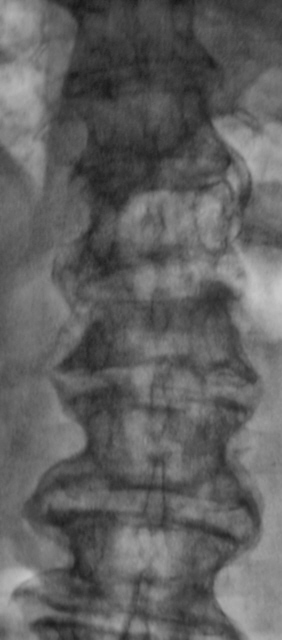

Позвонили из хирургического отделения, чтобы на передвижном аппарате (предназначен только для снятия конечностей) произвели рентгенограммы "грудного отдела позвоночника". Так как, что-то не нравится неврологу. Пациент находится в отделение с диагнозом "Кишечное кровотечение"...

Коллегам было разъяснено "где зад, а где перед", а также для чего нужен передвижной аппарат, и с учетом состояния пациента было предложено доставить в рентгеновский кабинет для полноценного рентгенологического исследования. С пациентом поговорил что болит и когда заболело. Пациент (весьма преклонного возраста мужчина) поведал, что месяц тому упал, и потом отказали ноги. произвели исследование - рентгенографию, "подключили" линейную томографию.

L1 сломал недавно, а L4 - давно

Да. Л1, по всей видимости, и сломали 1 месяц тому.

перелом Л1. Деформирующий спондилёз поясничного отдела позвоночника.